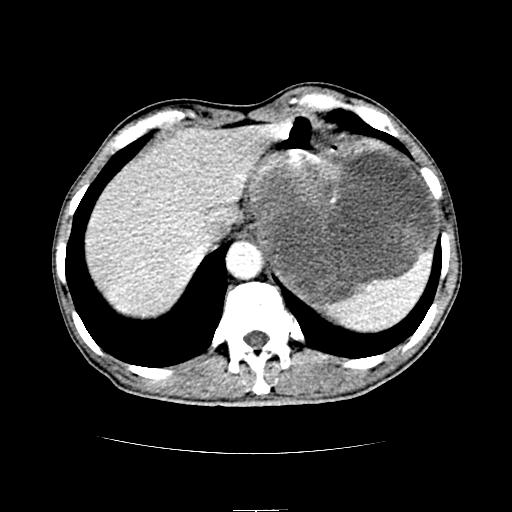

左上腹胃、脾及胰腺间巨大囊性占位性病变,内见多数薄隔,有轻度强化,明显占位效应。左肾见一小囊肿。

考虑:1、左上腹巨大囊肿(可能来源于胰腺)。

2、左肾小囊肿。

左上腹胃、脾及胰腺间巨大囊性占位性病变,内见多数薄隔,有轻度强化,明显占位效应,胰腺及左肾结构清楚,明显向后下方推压 移位。左肾见一小囊肿.多考虑:1 网膜巨大囊肿。2 左肾小囊肿。

1胃脾胰之间一巨大囊性影,胃明显向前推移,胰体尾部似肥大,考虑囊性影来源于胰腺(假性囊肿?)2左肾小囊肿。

左上腹囊性占位,与胰腺分界不清,考虑起源于胰腺可能。

左上腹囊性占位,虽与胰腺分界不清,胰尾似乎受压前移,病灶最大截面并不在胰腺水平,考虑来源于网膜可能性大吧,应再详细追问病史.